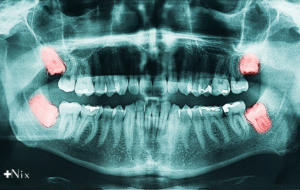

دندانپزشک برای بررسی دقیق وضعیت دندان عقل، دهان شما را معاینه میکند و در صورت نیاز از عکسهای رادیولوژی مانند OPG یا CBCT کمک میگیرد تا زاویه و محل دندان را بسنجد.